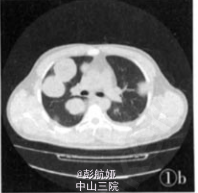

患者,男,34岁。以呼吸困难咳嗽咳痰伴上腹痛1周为主诉于2006年9月25日入院。发病时深呼吸咳嗽后胸口隐痛,痰中带血。血生化检查示:C反应蛋白22.4 mg/L(正常值0—8 mg/L)。心肌酶谱:谷草转氨酶46 U/L,乳酸脱氢酶2085 U/L,磷酸肌酸激酶57 U/L,肌酸激酶同工酶52 U/L,羟定酸脱氢酶192 U/L。凝血检查示:凝血酶原国际标准化比值1.01,凝血酶原正常对照12.90,凝血酶原时间13.0。外院完善寄生虫病原学检查示:痰虫卵(一),血清囊虫抗体弱(+),肺吸虫抗体(一),血吸虫抗体(一)。肿瘤四项检查示:AFP:328.1μg/L,CAl25:1.8μg/L,CAl99(一)。影像学检查示:B超“双乳头下3 cm×3 cm实性肿块,双腋下淋巴结肿大,颈部、手臂内侧、颅侧额叶左侧枕叶多发占位,肺部多发类圆形占位,肝脏脾脏多发占位,考虑为肝癌,颅内及肺内转移,不排除寄生虫病可能”,2006年10月1日行手臂肿块活检。

病理诊断:男性绒毛膜癌,并发肝、肺、脑、手臂转移。本例并发肝、肺、脑、手臂多处转移灶,已经出现胸、腹部症状,经化疗无效,最后出现呼吸衰竭自动出院。

绒毛膜癌为一种高度恶性的肿瘤,常继发于葡萄胎、流产或足月分娩以后,其发生比率约为2:1:1,故患者多为生育年龄妇女,少数也发生于绝经后妇女或男性。发生于绝经后是因为滋养细胞可在隐匿(处于不增殖状态)多年后开始活跃生长,其原因不明。绒癌多数发生在子宫,但也有未发现子宫内原发灶而只出现转移灶者。绒癌主要经血行播散发生远处转移,转移早而广泛,最常见转移部位是肺(80%),其他依次为阴道(30%)、脑(10%)、肝(10%)